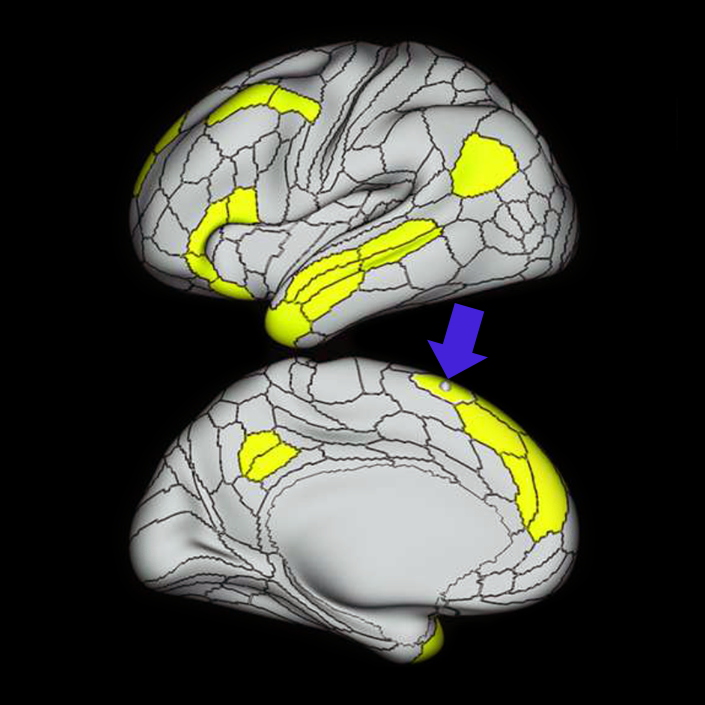

ᐅ SummaryArea SFL: part of the supplementary motor regions. Known to be hemispherically asymmetric. Specifically, the left hemisphere shows more activity when listening to stories and when a participant is matching objects based on a verbal cue. Compared to area 8BL, area SFL shows more activation when listening to a story, matching objects based on verbal cues and in social interaction settings. Compared to area s6-8, area SFL shows more activation in the left hemisphere when individuals listen to a story. In the right hemisphere, area SFL is activated insocial interaction settings and is deactivated during object feature comparison tasks. ᐅ Where is it?Area SFL (superior frontal language area) is located on the posterior medial SFG straddling over the interhemispheric cleft. ᐅ What are its borders?Area SFL borders SCEF inferiorly. Its anterior inferior neighbor is area 8BM and its anterior superior neighbor is area 8BL. Areas 6ma and s6-8 are its lateral neighbors. ᐅ What are its functional connections?Area SFL demonstrates functional connectivity to areas 8BL, 8AV, 9a, 9p, and 9m in dorsolateral frontal lobe, areas 8BM, d32, areas 44, 45, 47L, and 47s in the inferior frontal lobe, area 55b in the premotor areas, areas STSda, STSdp, STSva, STSvp, TE1a, and TGd in the temporal lobe, area PGi in the lateral parietal lobe, and areas 31pv, and 31pv in the medial parietal lobe. ᐅ What are its white matter connections?Area SFL is structurally connected to pyramidal tracts, the frontal aslant tract and contralateral hemisphere. Connections to pyramidal tracts descend through the posterior limb of the internal capsule and cerebral peduncle to the brainstem. The FAT connects SFL with the inferior frontal gyrus, terminating at parcellations 44, IFSp and MI. Contralateral connections course through the body of the corpus callosum to SCEF and 8BL. Local short association fibers connect with SCEF, 8BL, SFL and 6ma. ᐅ What is known about its function?Area SFL was subdivided from adjacent parcellations due to differences in myelin thickness and functional activity. Area SFL is known to be hemispherically asymmetric. Specifically, the left hemisphere shows more activity when listening to stories and when a participant is matching objects based on a verbal cue. Compared to area 8BL, area SFL shows more activation when listening to a story, matching objects based on verbal cues and in social interaction settings. Compared to area s6-8, area SFL shows more activation in the left hemisphere when individuals listen to a story. In the right hemisphere, area SFL is activated in social interaction settings and is deactivated during object feature comparison tasks. |

A: lateral-medial

B: anterior-posterior

C: superior-inferior

DTI image |